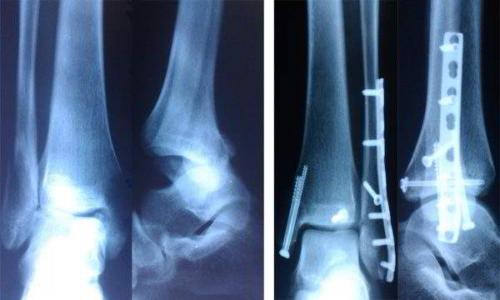

Артодез на этом суставе могут проводить как под общей, так и под спинальной анестезией. Для сращивания могут использовать специальные шурупы, винты, пластины, стержни, костные трансплантаты и другие медицинские приспособления для фиксации.

Также при выполнении артродеза к двум костям могут прикрепляться металлические импланты (винты, стержни, пластины на шурупах и др.). Это делается для того, чтобы удерживать кости в неподвижном положении, благоприятствующем росту новой кости.

При артродезе голеностопного сустава может использоваться каждый из этих методов.